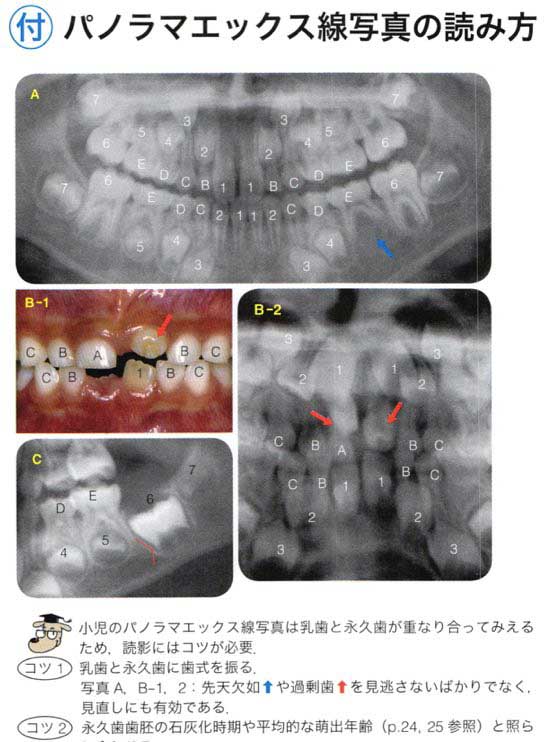

6歳の男児。定期診査を希望して来院した。来院時のエックス線写真を別に示す。

適切な所見はどれか。2つ選べ。

a Hellmanの歯齢はⅢA期である。

b 下顎切歯が1歯不足している。

c 犬歯の歯冠の位置は正常である。

d 下顎第二小臼歯が1歯不足している。

e 第一大臼歯の歯根形成は遅延している 。

正答 b,c

a ヘルマンの歯齢が悩みます。6も1も萠出途中だし、どっちだったっけ、ⅡCだったかⅢAだったか。。。そもそも、ⅡCとⅢAの明確な違いってなんだっけ。。。

x線の所見は本当に見慣れていないときついです。「c 犬歯の歯冠の位置は正常である。」って自身持って選べる学生は少ないと思います。臨床でがっつり症例こなしたりすると自然に身につくようなもんでしょうけど、学生で教科書にのっている数枚のレントゲンしか見ていない状態だときついものがあります。

以上を踏まえて問題のレントゲンを見てみると、、、上下6が萌出途中で、噛み合っていませんよね!ということで、これはⅢAになれていないので、ⅡCだと一発で判断することができます!

実は、国家試験の正答は間違っています。選択肢の「d 下顎第二小臼歯が1歯不足している。」が、誤答肢になっていますが、これは実は正しいです。パノラマをよく見てみると右下5の歯胚が薄くですが、でき初めています。この感じだと左下5も今後でてくる可能性は十分にあります。

御存知の通り、先天欠如の多い歯種は「8」「5」「2」ですね。それぞれ、「大臼歯」「小臼歯」「切歯」でもっとも遠心にある歯は退化傾向で、先天欠如が多いことで知られています。この問題のパノラマも「5」がその傾向にあり、下顎では歯胚の形成がすごく遅れており右下5のみ確認できます。上顎では左上5が正常に発生していますが、やはり右上5の歯胚は確認できません。

よって、本当はこの「d 下顎第二小臼歯が1歯不足している。」は微妙な選択肢で、最近の感じだと削除かこの選択肢も丸になる流れになると思います。クレームがついてもきちんとした反論はできないかと思わます。(一応、この内容は、大学の小児歯科の先生に確認とれていますし、ANSWERでは画像所見の欄にのみ指摘されています。)